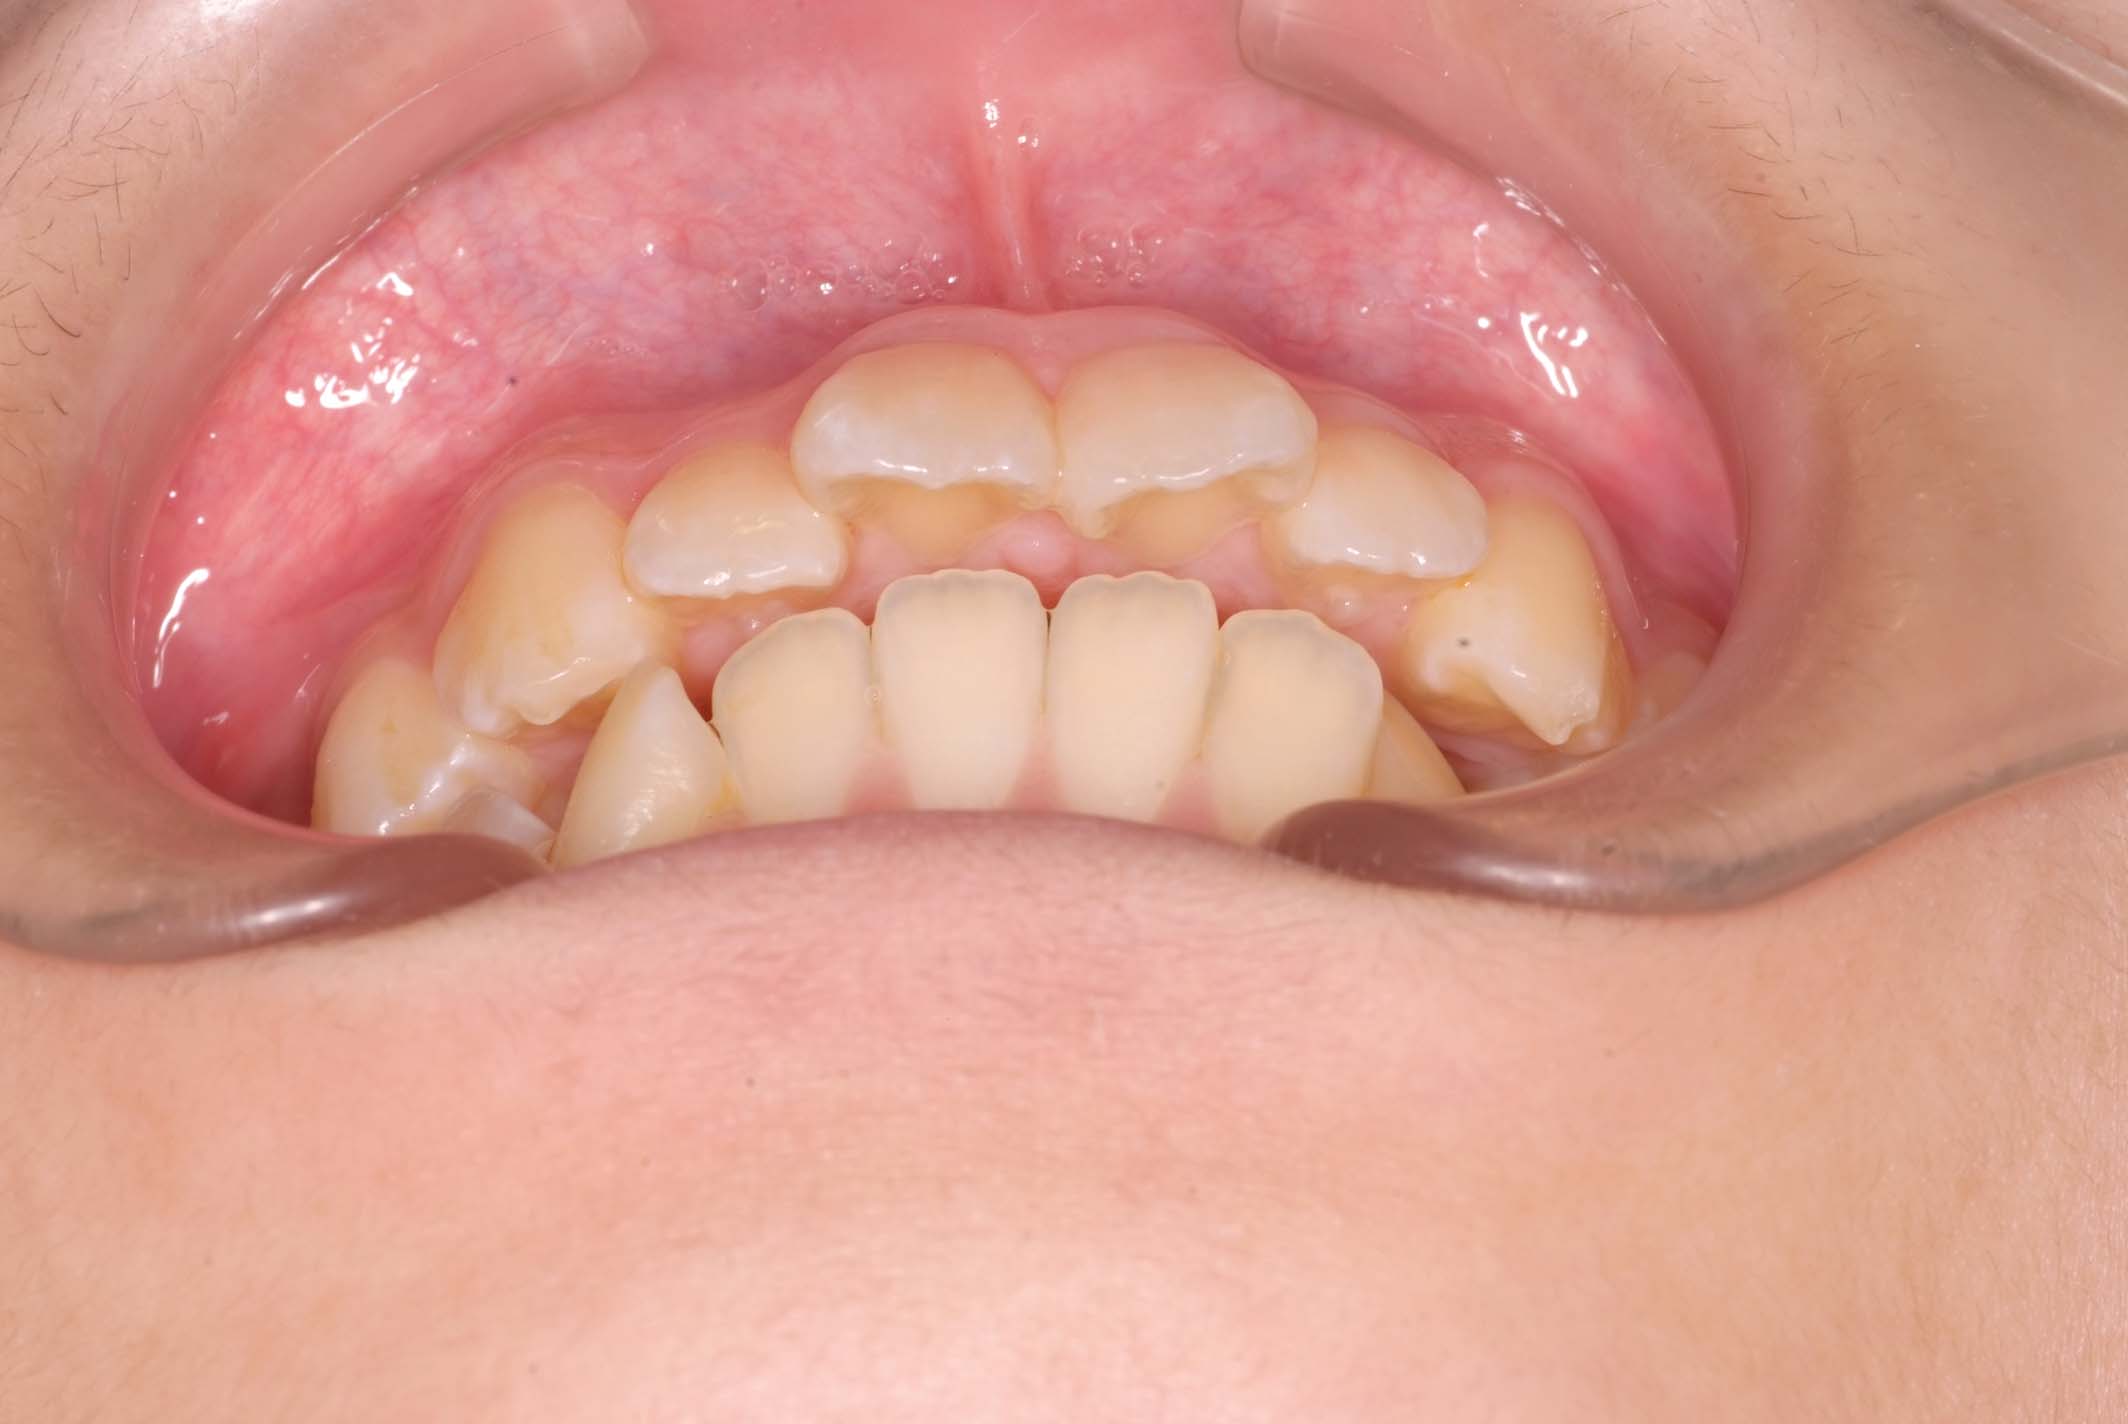

初診時年齢8才の女子で、前歯部開咬を気にして来院されました。

検査の結果、前歯部開咬と正中離開と上下顎前歯唇側傾斜を伴うアングルⅡ級1類不正咬合と診断しました。

前期治療は、リンガルアーチで正中離開を改善し、その後は歯列矯正用咬合誘導装置(マイオブレース)を使用して舌のトレーニングを行いました。後期治療は、上下左右4番を抜歯の上、セルフライゲーションブラケット装置(クリアティ・ウルトラ)で行いました。治療期間は前後期合わせて6年6ヶ月でした。通院回数:60回。